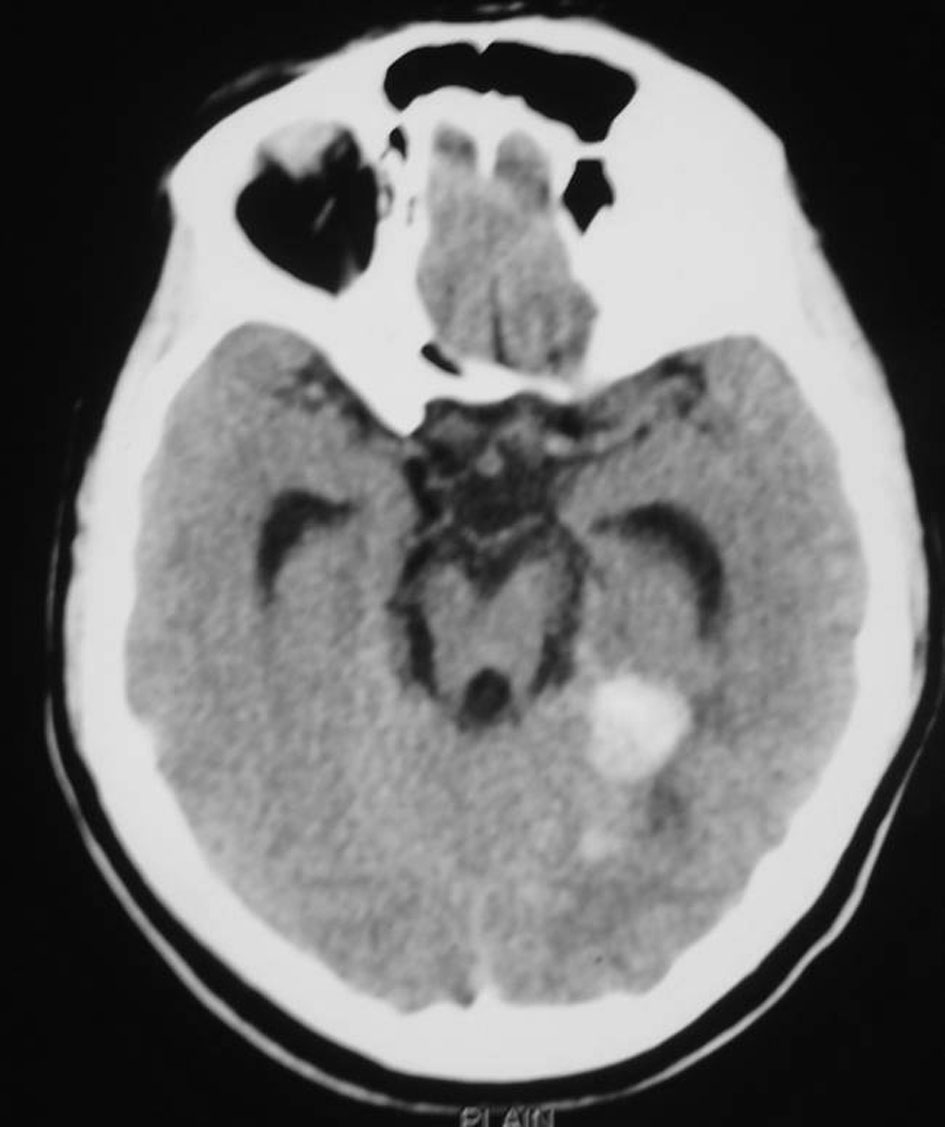

A 27-year-old lady married one and a half years before and conceived 4 months before was having a normal growth of the fetus as per the ultrasound report. At 2 months of gestational age she had sudden onset of severe global headache associated with vomiting and one episode of generalized seizures for which she sought treatment in another neurosurgical center. CT scan of the brain revealed diffuse subarachnoid hemorrhage and foci of bleed in the right medial posterior temporal region (Fig. 1). It was suspected to be an aneurysmal bleed and CT angiogram was done which did not show any evidence of intracranial aneurysm. As there was early hydrocephalus she underwent right VP shunt. Gynaecological opinion was sought and in view of unprotected radiation and increased risk of congenital fetal malformations, she also underwent medical termination of pregnancy.

![]() Click for large image | Figure 1. CT scan of the brain showing diffuse subarachnoid hemorrhage and foci of bleed in the right medial posterior temporal region. |